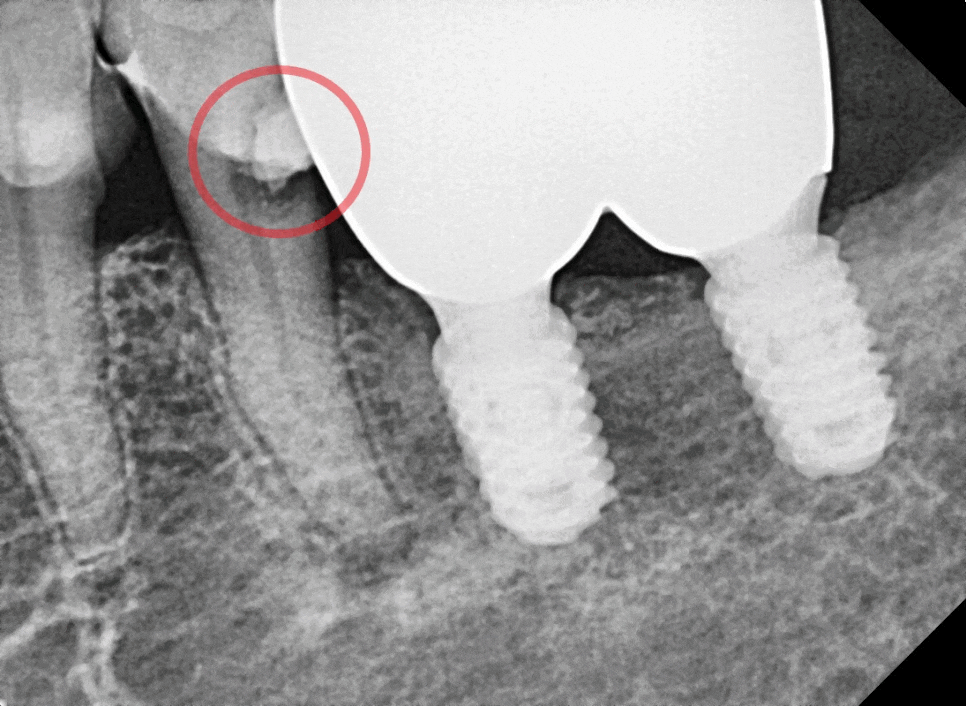

250321~250421

뿌리 신경의 길이를 끝까지 재서 소독하는 과정을 2~3번 거친 후 신경치료를 끝냈습니다.

250717 신경치료 후 크라운으로 마무리한 모습

신경치료 후, 약해진 치아가 깨지는 것을 방지하기 위해 크라운까지 씌워 치료가 마무리되었습니다.